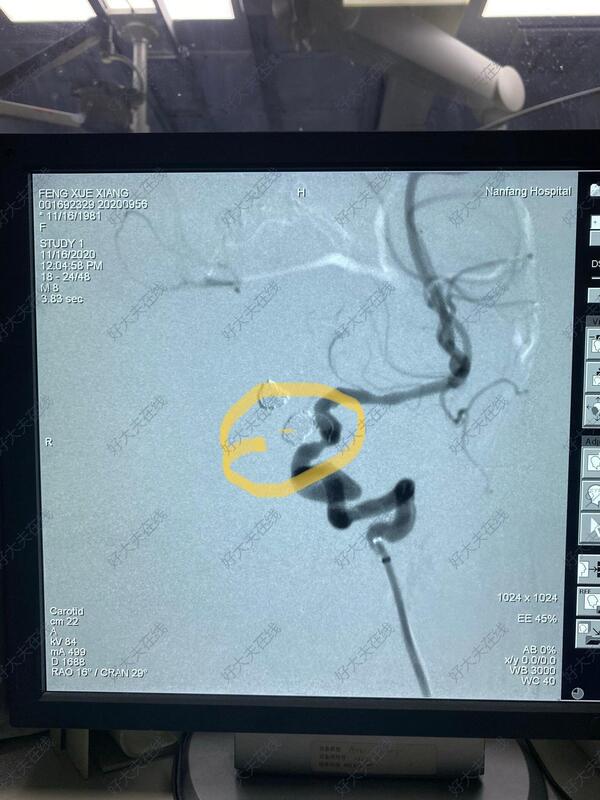

治疗后

现在动脉瘤已经致密填塞,拆除了“炸弹”,再破裂出血的机率已经几乎为0!下一步就是康复治疗了!